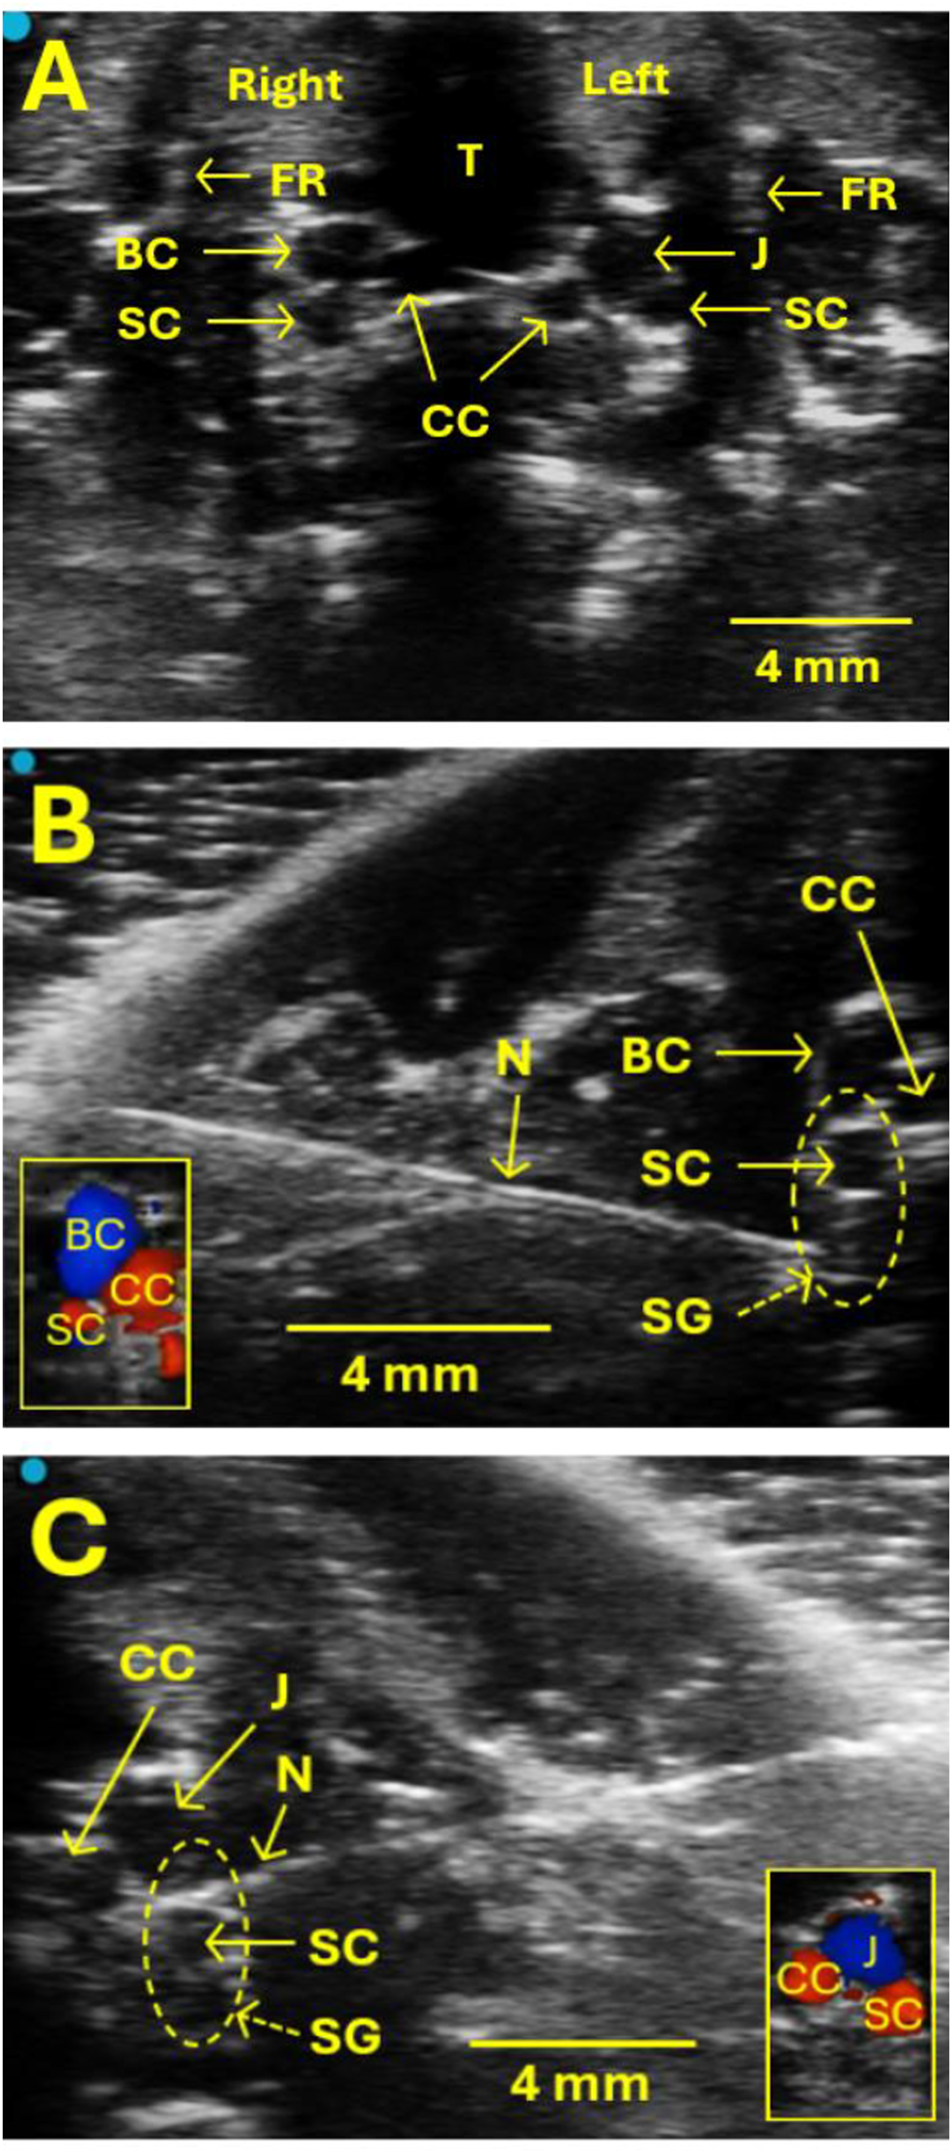

The regions around the clavicle and chest were shaved and cleaned. The skin was disinfected with a chlorhexidine disinfectant. The linear ultrasound transducer (MX250, FUJIFILM VisualSonics, Vevo 3100 LT imaging system) was placed at the heart’s position in the short axis view and moved anteriorly until the trachea, first rib, common carotid artery, the brachiocephalic or jugular vein, and subclavian artery could be seen (Figure 1A). These structures served as landmarks to help locate SG. SG was not visible but was located based on its surrounding structures mentioned above using ultrasound. In this respect, the SG is near the subclavian artery on both the right and left sides. The animal monitoring platform was integral in maintaining proper positioning for the ultrasound transducer and allowed for image fine-tuning (Vevo SR200).

FIGURE 1

Ultrasound images show the location of the SG for the injection. (A) The SG itself is not visible on ultrasound, but some valuable landmarks help locate SG and guide the SG injection safely without puncturing blood vessels. These landmarks include the trachea (T), the first rib (FR), the common carotid artery (CC), the brachiocephalic vein (BC), the jugular vein (J), and the subclavian artery (SC). The SG is located near SC on both the right and left sides. (B, C) Examples of images showing the SG injection on the right (B) and left (C) sides, respectively. Vertical oval areas formed by dot lines in B and C indicate SG locations. N indicates a needle. CC, BC, J, and SC were verified by Doppler examination, as illustrated in the small box in the lower left corner (B) and right corner (C).

After establishing a stable baseline of ultrasound monitoring for a 10-min interval, a 26-gauge hypodermic needle with a 1 mL syringe (marked every 10 µL) was advanced in-plane with the transducer from lateral to medial to the SG region (Figures 1B, C). At the proper injection site of the SG, the transducer should be in close proximity to the collarbone since SG is near the first rib. This served as an additional method to confirm the SG’s correct injection site. When the needle tip reached the target SG region, the syringe cylinder was withdrawn slightly to verify that no blood was present due to the procedure as executed to that point. A single injection of 1.0%–1.5% lidocaine or 0.9% normal saline mixed with Chicago blue dye at 40–60 µL was administered to the right or left SG. The administration of injected liquid was observed, and the injection process was monitored directly with ultrasound. After the administration, the needle was removed.